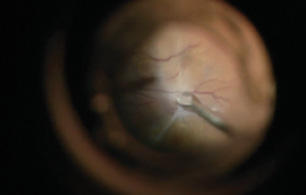

One shortcoming of the early systems was the amount of time needed to open and close the overlying conjunctiva and to suture sclerotomy openings to prevent postoperative hypotony. To improve efficiency and safety, the development of platforms with 23-, 25-, and 27-gauge instruments has allowed surgeons to perform transconjunctival sutureless PPV.4-6 These instruments are the new standard of care and are widely used today (Video 1).

With the transition to smaller-gauge PPV platforms, technologies for illumination, fluidics, and vitreous cutting also had to progress to allow safe and successful clinical outcomes. Faster cutting speeds and miniaturization of the vitrector probe have translated to safer posterior segment surgery. Additionally, those faster cutting speeds, combined with smaller port openings, cause less traction on vitreous collagen fibers that can cause the retina to jump into the port. Thus, surgeons can maneuver close to the retina with less risk for iatrogenic breaks.

Currently, 7,500 cuts per minute (cpm) is the fastest commercially available speed for PPV platforms; development of a 10,000 cpm system is well under way, and this capability may be introduced soon.